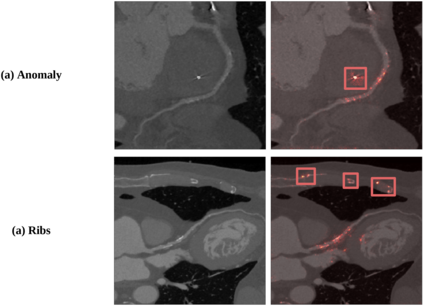

To decrease patient waiting time for diagnosis of the Coronary Artery Disease, automatic methods are applied to identify its severity using Coronary Computed Tomography Angiography scans or extracted Multiplanar Reconstruction (MPR) images, giving doctors a second-opinion on the priority of each case. The main disadvantage of previous studies is the lack of large set of data that could guarantee their reliability. Another limitation is the usage of handcrafted features requiring manual preprocessing, such as centerline extraction. We overcome both limitations by applying a different automated approach based on ShuffleNet V2 network architecture and testing it on the proposed collected dataset of MPR images, which is bigger than any other used in this field before. We also omit centerline extraction step and train and test our model using whole curved MPR images of 708 and 105 patients, respectively. The model predicts one of three classes: 'no stenosis' for normal, 'non-significant' - 1-50% of stenosis detected, 'significant' - more than 50% of stenosis. We demonstrate model's interpretability through visualization of the most important features selected by the network. For stenosis score classification, the method shows improved performance comparing to previous works, achieving 80% accuracy on the patient level. Our code is publicly available.